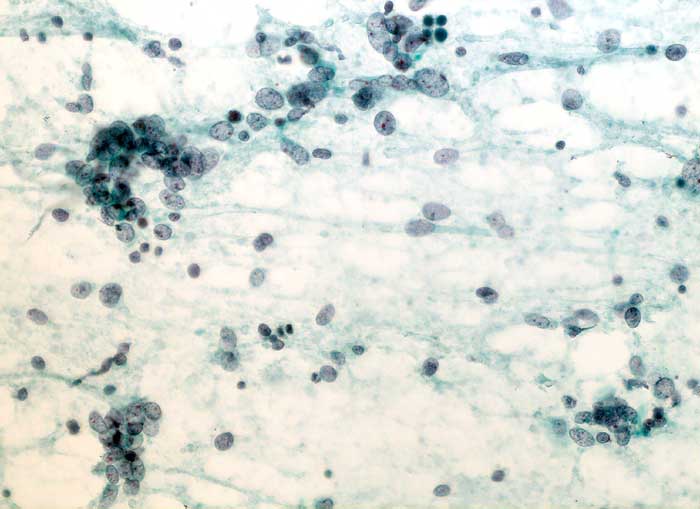

PathoPic – image database / PathoPic ID 6285 - Adenosarkom

Adenosarkom

maligner Tumor

Uterus

Uterus, Frischgewebsausstriche: Zahlreiche vielfach nacktkernige Zellen eines teils spindelzelligen malignen Tumors. Die Spindelzellen sind sehr unterschiedlich gross. Die Kerne sind längsoval, hyperchromatisch und weisen einen oder mehrere Nukleolen auf. Die Zellen liegen einzeln oder zu kleinen Gruppen zusammengeballt. Detritischer Hintergrund.

Zytologische Diagnose: Zahlreiche Zellen eines teils spindelzelligen malignen Tumors.

Der spindelzellige, teils deutlich sarkomatoide Aspekt spricht am ehesten für einen malignen Mischtumor.

Zytologie

200